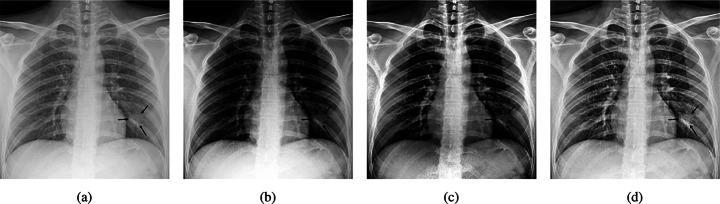

One of the primary clinical observations for screening the novel coronavirus is capturing a chest x-ray image. In most patients, a chest x-ray contains abnormalities, such as consolidation, resulting from COVID-19 viral pneumonia. In this study, research is conducted on efficiently detecting imaging features of this type of pneumonia using deep convolutional neural networks in a large dataset. It is demonstrated that simple models, alongside the majority of pretrained networks in the literature, focus on irrelevant features for decision-making. In this paper, numerous chest x-ray images from several sources are collected, and one of the largest publicly accessible datasets is prepared. Finally, using the transfer learning paradigm, the well-known CheXNet model is utilized to develop COVID-CXNet. This powerful model is capable of detecting the novel coronavirus pneumonia based on relevant and meaningful features with precise localization. COVID-CXNet is a step towards a fully automated and robust COVID-19 detection system.

筛查新型冠状病毒的主要临床观察方法之一是拍摄胸部X光图像。在大多数患者中,胸部X光显示出由COVID-19病毒性肺炎引起的异常,如实变。在本研究中,我们利用深度卷积神经网络在一个大型数据集中对这种类型肺炎的成像特征进行高效检测。结果表明,简单模型以及文献中的大多数预训练网络都关注于与决策无关的特征。本文收集了来自多个来源的大量胸部X光图像,并准备了一个最大的公开可用数据集。最后,使用迁移学习范式,利用著名的CheXNet模型开发了COVID-CXNet。这个强大的模型能够基于相关且有意义的特征精确地定位检测新型冠状病毒肺炎。COVID-CXNet朝着全自动且强大的COVID-19检测系统迈出了一步。